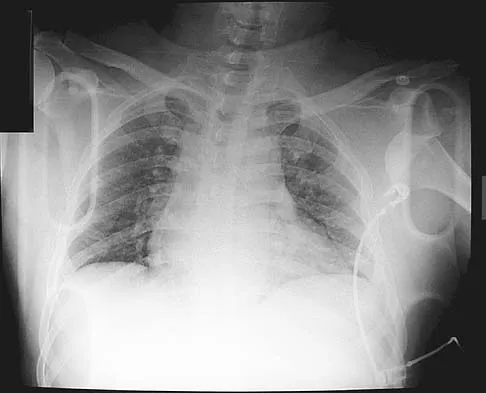

A 25-year-old patient who sustained multiple bilateral rib fractures, a pulmonary contusion, a left nondisplaced transtectal acetabular fracture, and a closed humerus fracture in a motor vehicle accident 2 weeks ago is transferred from another hospital. The humerus fracture has been surgically treated. There are no signs of infection, and the trauma surgeon wants to mobilize the patient as soon as possible. Radiographs are shown in Figures 15a and 15b. Management of the humerus fracture should consist of

Explanation